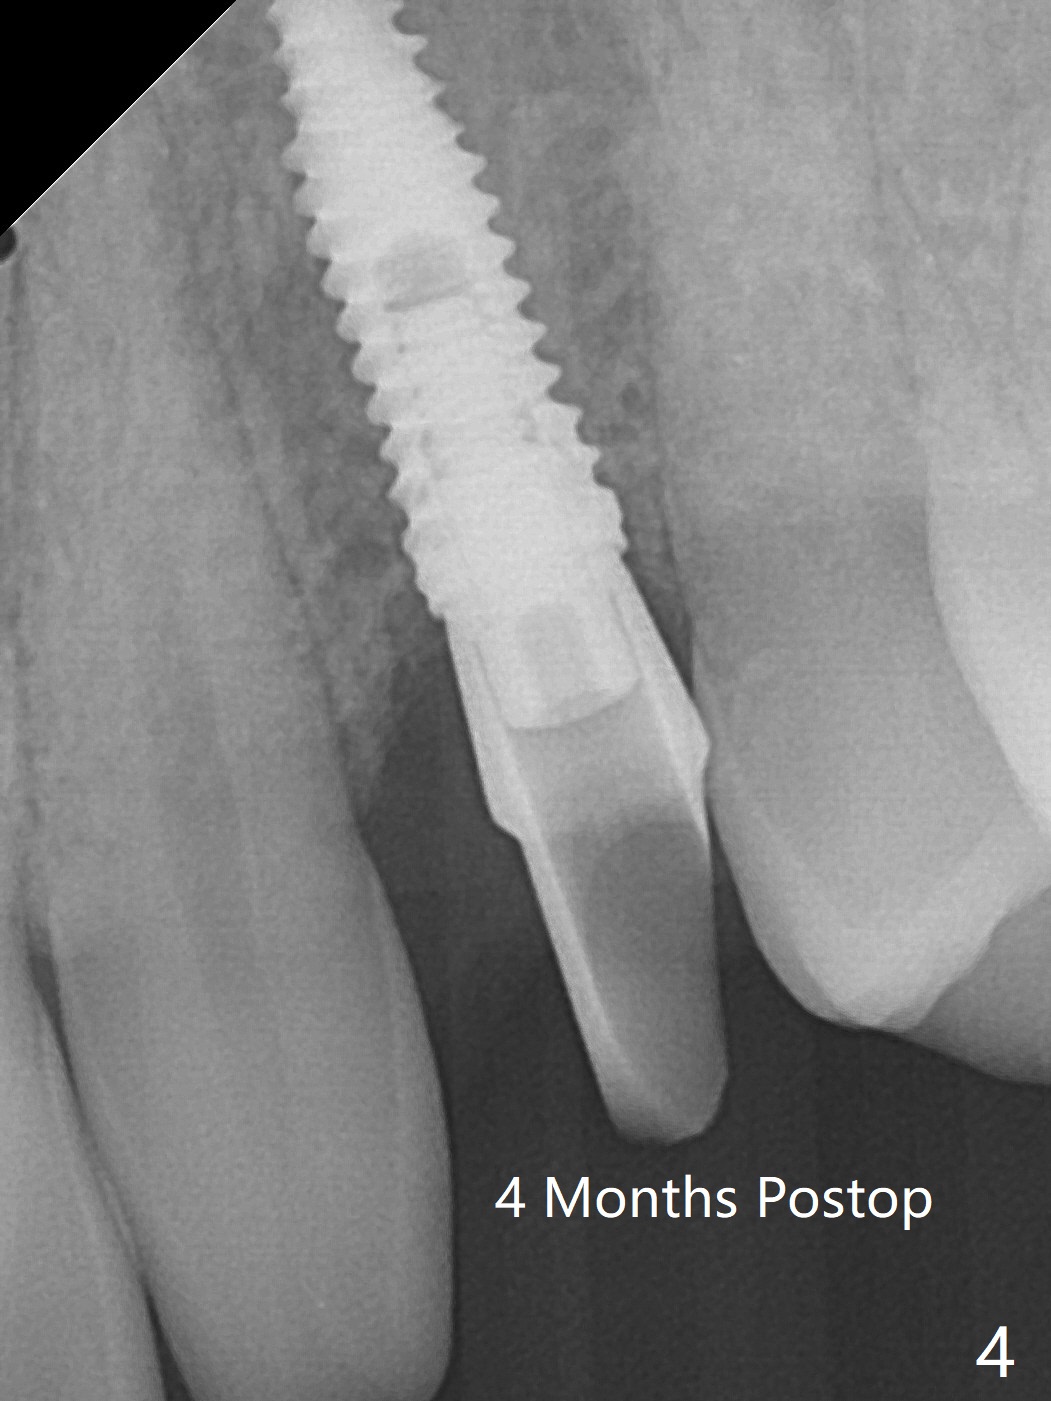

When the guide with 10.5 mm offset is seated at #11 after extraction, it looks buccal. Pointed drill creates an entry point in the mesial portion of the socket. PA, taken following 2.2x11.5 mm drill, shows acceptable mesiodistal trajectory (Fig.1). When a 3.5x11.5 mm implant is placed, it is difficult to withdraw the driver from the metal tube (Fig.1 *). There is no buccal gap with plenty of the lingual gap. A 4x3 mm x15 degree A-type angled abutment is placed (Fig.2). It appears that the dense palatal plate deviates the osteotomy and implant placement (as compared to the design, Fig.3). In fact osteotomy should have been prepared until 4 mm in diameter before increase in depth with 2.2 and 3 mm drills to eliminate buccal deviation. The ideal drill sequence would be point drill, 2.2x8.5 mm drill, 3x8.5, 3.5x8.5, 2.2x10, 2.2x11.5, PA to confirm trajectory, 3x10, 3x11.5 and 3x13. Torque associated with implant placement is pure, not derived from friction between the driver and the metal tube. There is mesial crestal bone loss 4 months postop (Fig.4, as compared to immediate postop in Fig.2 (*)). Crestal bone loss does not get worse between 4 and 6.5 months postop (Fig.4,5). The bone density increases 8 months post cementation (Fig.6).